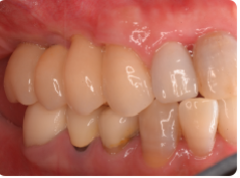

歯周病が進行し、グラグラして物が嚙めず、抜歯してインプラントにしていくことに。

インプラントはストローマンを使用、上部構造はジルコニアセラミックス

費用は2本で総額40万円(税込44万円)(他院の相場だと税込88万円位です)